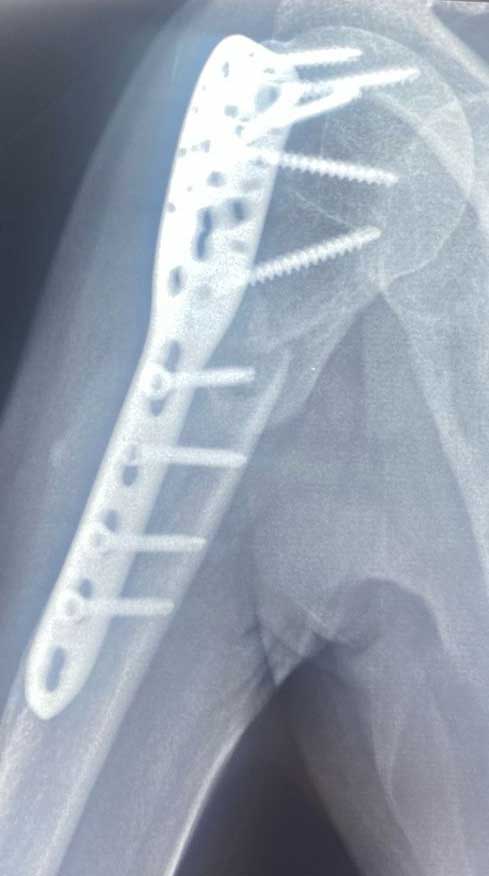

Fractura

de hombro

Pérdida de la continuidad del tejido óseo de la articulación del hombro, articulación acromioclavicular o cintura escapular, las cuales están constituidas por humero, escápula y clavícula.

¿Por qué se realiza?

El tratamiento puede ser quirúrgico o conservador (no quirúrgico) el cual estará determinado por las características del paciente, el hueso fracturado y el desplazamiento de los fragmentos, el cual puede consistir en inmobilizaciones o cirugías abiertas, mínima invasivas ó artroscopicas.

Es necesario cuidar la osteosíntesis del hombro por semanas después de la cirugía, apegado a la terapia física frecuente para evitar el dolor del edema y rigidez postquirúrgica. Los protocolos para la rehabilitación del hombro quirúrgico están muy bien protocolizados y estandarizados para mejorar el resultado y varían de 4-12 semanas.

Resultados esperados

En cuanto a fracturas de hombro es decir del humero proximal, escápula o articulación glenohumeral es importante siempre tener en cuenta el grado de la lesión, es decir, la complejidad del numero de estructuras óseas y si afecta o no la articulación, y si es una fractura con múltiples fragmentos. Pero la intención de una cirugía es siempre conseguir el mejor resultado funcional para mejorar la calidad de vida del paciente.